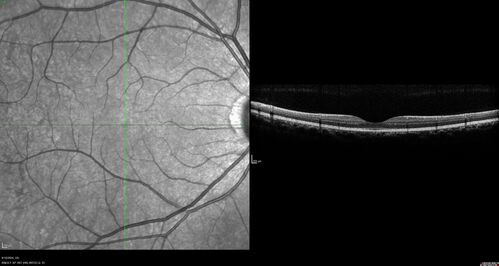

| Filename: | Normal-OCT_Line_Scan_28229.jpg |

| Album name: | scohen125 / Normal 28 year old female with migraine |